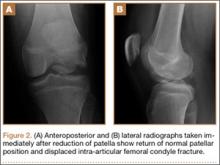

After reduction, an immediate return of normal patellar contour and patellofemoral tracking was observed as the knee was gently extended. There was no obvious defect to the patellar or quadriceps tendons, and the patient was able to perform a straight-leg raise, confirming the integrity of the extensor mechanism. Radiographs performed after the reduction confirmed relocation of the patella in correct anatomic position, as well as a lateral femoral condyle fracture (Figures 2A, 2B). Magnetic resonance imaging (MRI) of the knee confirmed no full-thickness quadriceps or patellar tendon tear. A computed tomography (CT) scan of the knee showed a comminuted fracture of the lateral femoral condyle in the coronal plane, as well as multiple bone fragments within the joint (Figures 3A, 3B). The patient was placed in a bulky soft dressing and underwent open reduction and internal fixation of the fracture.